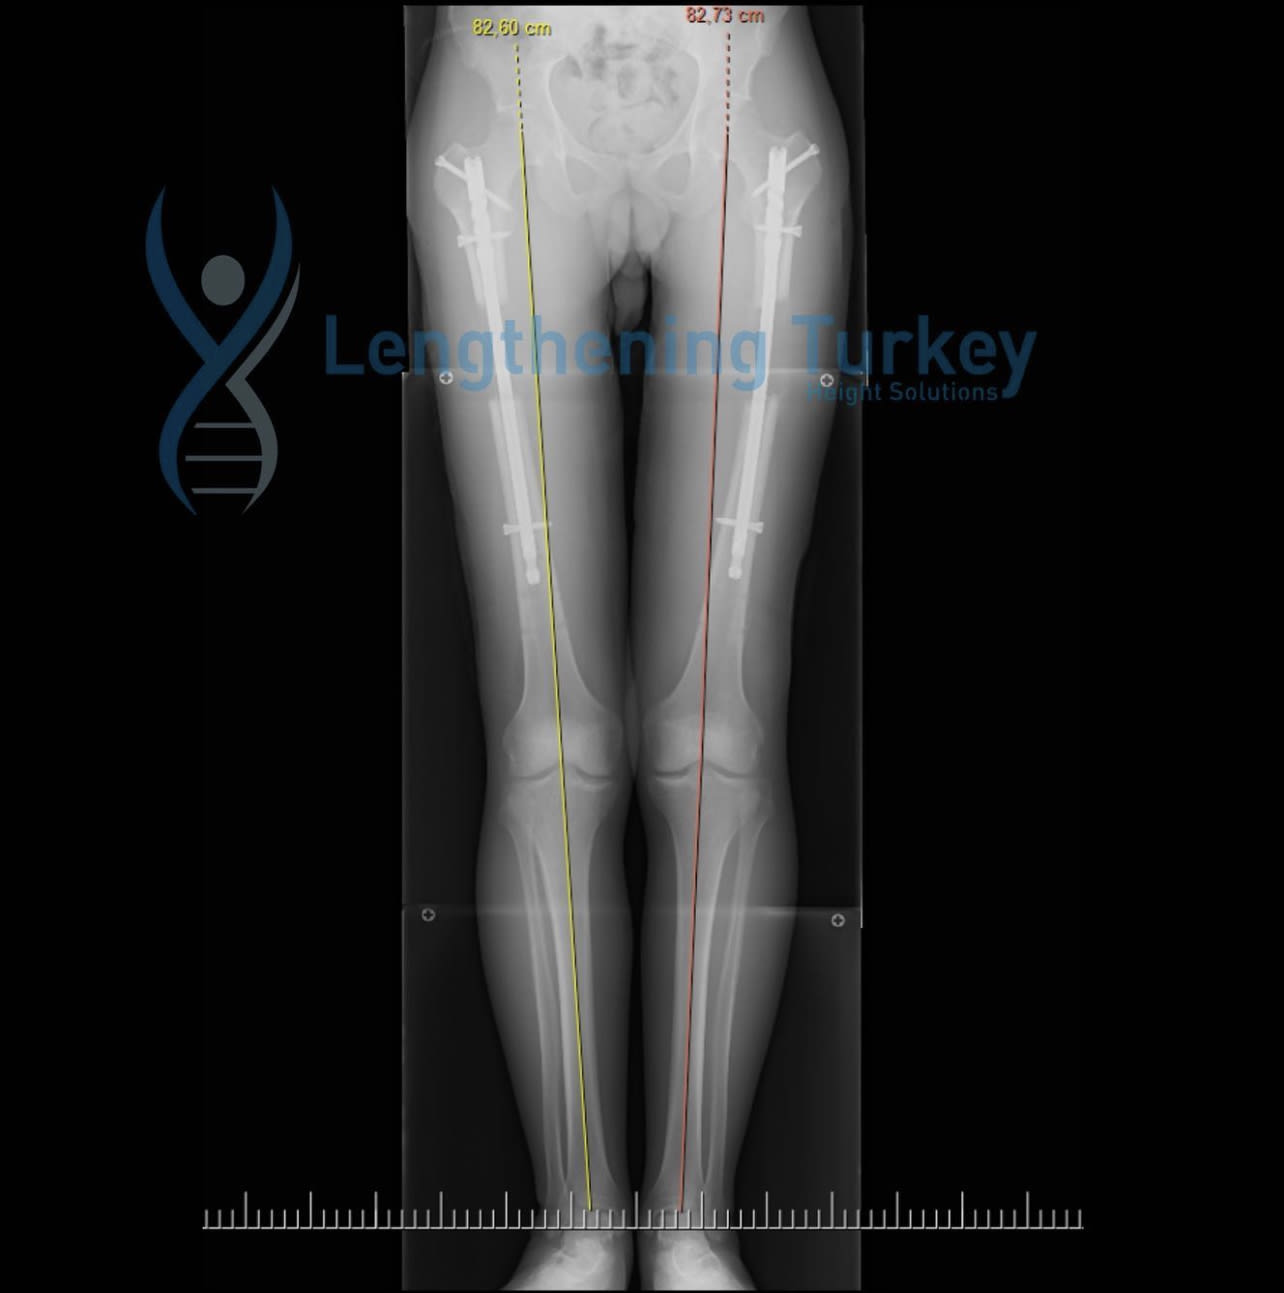

还末迟!你还可以增高8cm/3吋

LENGTHENING TURKEY HEIGHT SOLUTIONS 助你三个月内增高